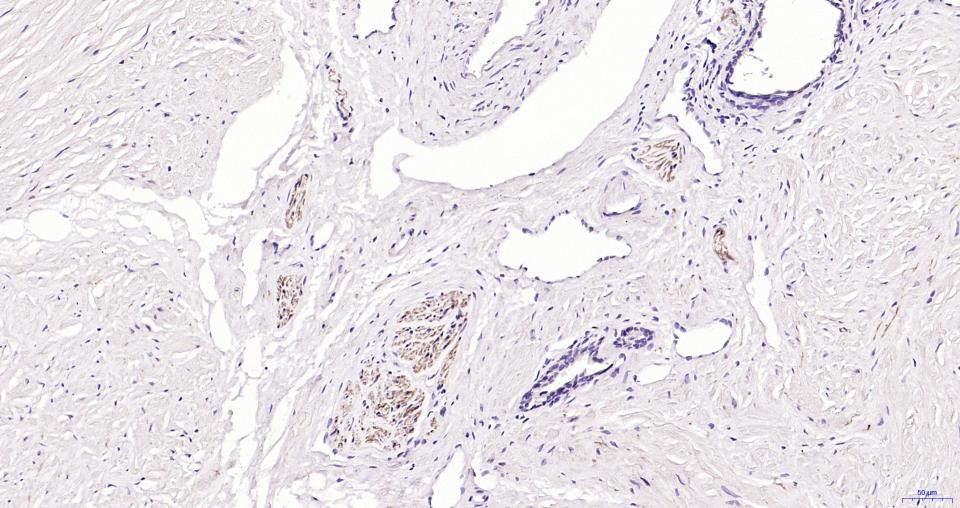

细胞粘附蛋白(Call Adhesion Protein) 神经元标志物 NCAM-1为神经细胞粘附分子,主要分布于神经组织,神经—肌肉接头,神经—内分泌腺和某些内分泌腺以及大多数神经外胚层来源的细胞、组织和肿瘤中。 NCAM 1主要用于视网膜母细胞瘤、髓母细胞瘤、星形细胞瘤、神经母细胞瘤等肿瘤方面的研究。CD56(神经细胞黏附分子,NCAM)表达于大部分神经外胚层来源的细胞系、组织和肿瘤如视网膜母细胞瘤、成神经管细胞瘤、星形细胞瘤以及成神经细胞瘤。它也表达于一些中胚层来源的肿瘤如横纹肌肉瘤。NK细胞以及NK细胞淋巴瘤为阳性。CD56被认为是NK细胞肿瘤的重要标志物。该抗体识别分子量为180,145和125kDa亚型。